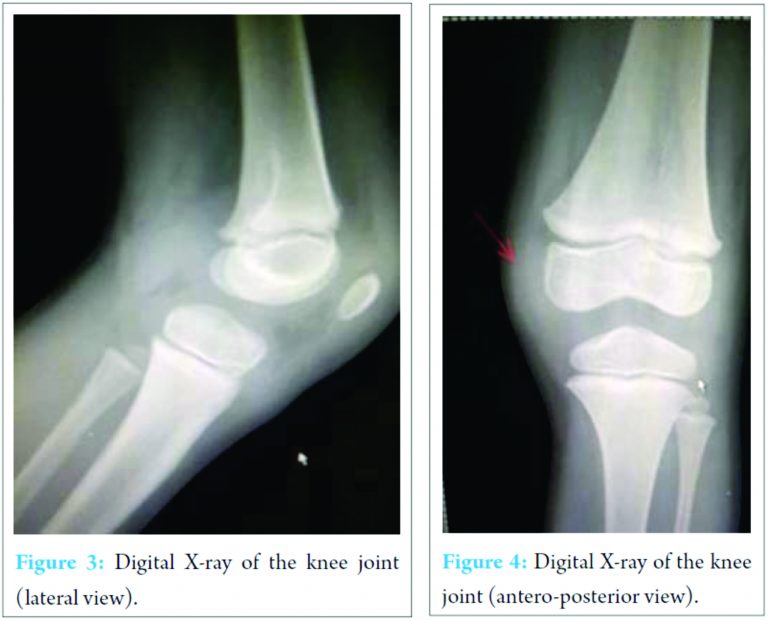

X-ray of the knee joint was unremarkable (Fig. 3, 4). Ultrasonography (USG) revealed a hypoechoic well-defined cystic lesion with clear contents is visualized on the antero-medial aspect of the left knee over the semitendinosus tendon. The lesion measures 25 mm × 10 mm. The lesion is causing splaying of the gracilis and sartorius muscles near knee; the lesion extends lower down and posteriorly and appears to fuse close to pes anserine insertion near the pulsation of the medial geniculate artery (Fig. 5, 6). Doppler USG showed no evidence of vascular involvement.